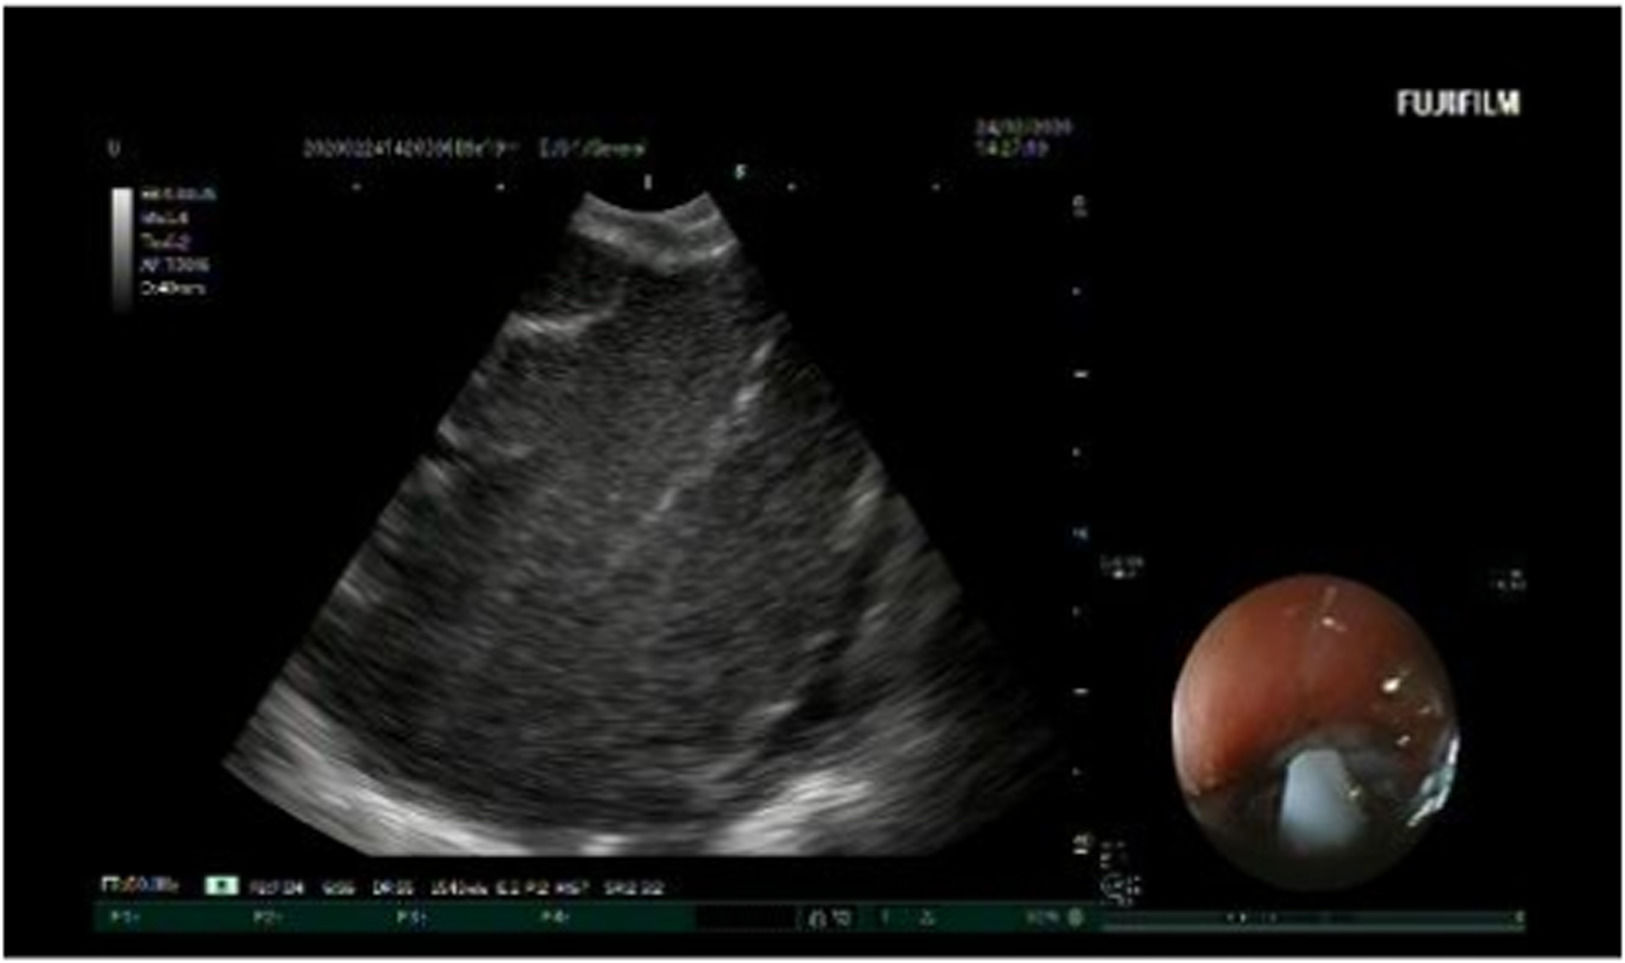

EBUS was performed under general anesthesia. The pulse rate, respiratory rate, oxygen saturation, and blood pressure were monitored throughout the procedure. A Convex-Probe Endobronchial Ultrasound (CP-EBUS) scope (Fujifilm, Ultrasonic Processor SU-1) with a 7.5 MHz convex transducer was used. The ultrasonic processor processed B-mode and color-power Doppler images. CP-EBUS was performed orally. International Staging System guidelines for lung cancer were followed to identify the LNs. After identifying the node with EBUS, the vascular structures were detected using the Doppler mode. The images were captured during a real-time Transbronchial Needle Aspiration (TBNA) session (Fig. 1). The authors used a 22-gauge cytology needle to obtain specimens. The samples obtained from the LNs were spread on glass, and fixed with 95% alcohol and formalin. These were then sent to the Pathology Department, and the pathology results were obtained. The patient’s images were classified as malignant or benign, according to the pathology results. Based on the expert visual interpretation of pulmonologists, each image was evaluated independently by the same observer.

ResultsThe dataset comprised 310 EBUS images from 62 patients (Fig. 3). To increase the power of the dataset, each image was subjected to 36 rotations and 10 distortions. Thus, a total of 14,570 images were acquired for the dataset. 20 % of the dataset was used for testing, while the remaining 80 % was used for training. Patient characteristics and data are given in Table 1.